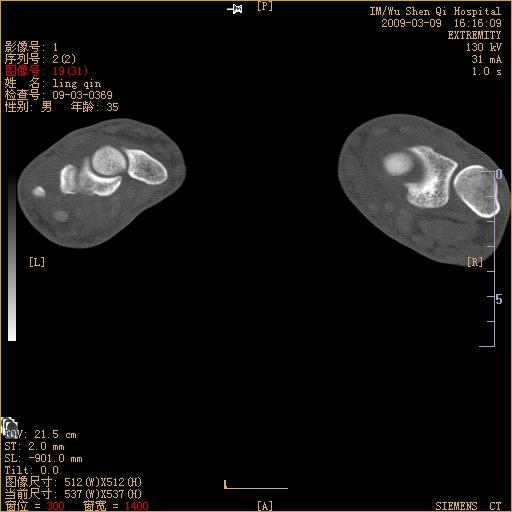

标题: CT18570:右手外伤10余天

请上传x线平片。舟状骨骨折可能大。

腕部有骨折、脱位,骨科面对ct片如何采取措施?三维一下。

请上传x线平片,腕骨多骨骨折

舟状骨骨折。

左侧舟骨及桡骨茎突骨折,第一掌骨基底部好像也有骨折,建议上传平片